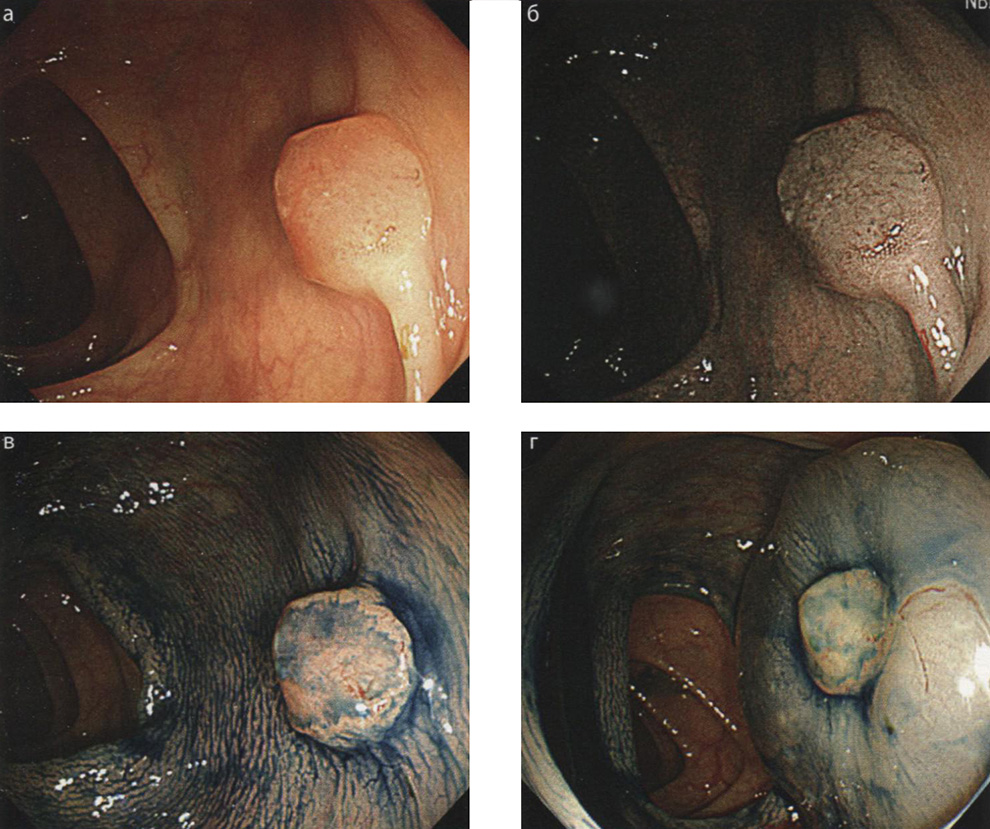

- Тем не менее следующие терапевтические техники могут быть предложены при подтвержденном или предполагаемом малигнизированном колоректальном полипе — эндоскопическая диссекция в подслизистом слое (ESD) и хирургическое лечение (см. гл. 10, ESD при колоректальной неоплазии). Как правило, не приподнимающиеся, «сидячие», полипы ассоциируются с массивной инвазией рака, что является абсолютным противопоказанием к полипэктомии при колоноскопии (рис. 9.1).

Рис. 9.1. Признаки отсутствия лифтинга малигнизированного «сидячего» полипа: а — образование диаметром 10 мм, тип 0—Is в нисходящей ободочной кишке. Осмотр в белом свете; б — узкоспектральная эндоскопия того же образования; в — изображение образования после окрашивания индигокармином; г — эффективное приподнятие полипа после введения раствора не достигнуто (признак отсутствия лифтинга малигнизированного полипа), это является противопоказанием к полипэктомии при колоноскопии